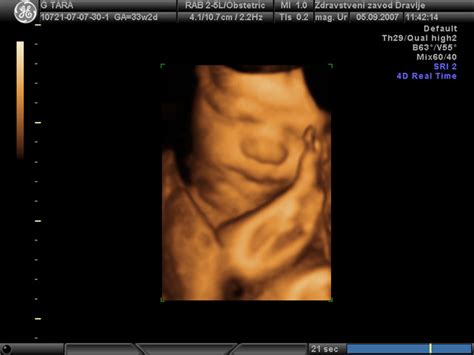

Poleg nuhalne svetline in morfologije potekajo v nosečnosti tudi redni kontrolni pregledi, običajno enkrat mesečno do 36. tedna nosečnosti, nato pa pogosteje. Ti pregledi vključujejo tehtanje nosečnice, merjenje krvnega tlaka, pregled urina, merjenje obsega trebuha in poslušanje plodovih srčnih utripov. Z ultrazvokom se lahko opazujejo gibanje ploda, meri njegova rast, po želji pa se lahko posnamejo tudi 3D slike ali 4D filmi.